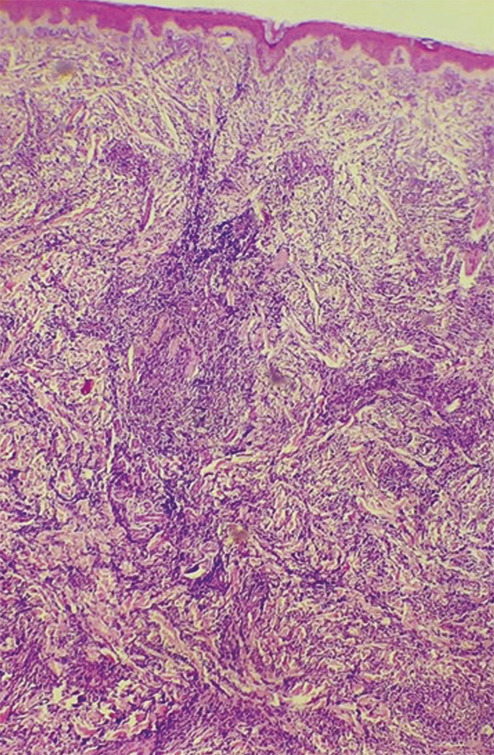

Après concertation pluridisciplinaire, dermatologues et chirurgiens décident d’une biopsie-exérèse. L’étude histologique révèle une infiltration blastique massive (fig. 2) avec expression des antigènes CD20 et CD3, aspect d’une prolifération lymphoïde en faveur d’une leucémie à localisation cutanée.